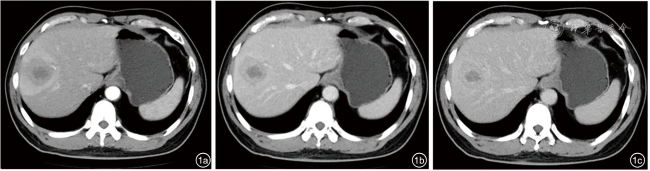

患者男性,42岁,右下腹酸胀疼痛3个月,无发热、寒战、周身黄染等其他症状,无肝炎病史。深圳市人民医院门诊CT检查发现肝右叶一类圆形低密度影,边界欠清楚,大小约4.5 cm×4.2 cm,增强扫描呈填充式强化,内壁欠光整,病灶内见小片状无增强区,动脉期病变周围见异常灌注(图1)。CT提示:肝右叶占位,考虑肝脓肿可能性大,肿瘤性病变待排查。实验室检查:直接胆红素浓度为8.5 μmol/L,总胆红素浓度为30.7 μmol/L,丙氨酸氨基转移酶40.1 U/L,碱性磷酸酶125 U/L,其余指标均在正常范围内。中性粒细胞比值、中性粒细胞绝对值在正常范围内,肿瘤标志物癌胚抗原、甲胎蛋白、糖类抗原199均阴性。入院行抗感染治疗1周后复查超声:肝右前、后叶交界处可见一大小约4.9 cm×4.6 cm实质性团块,形状欠规则,内部为不均质低回声,边界尚清楚,无声晕,彩色多普勒血流成像见团块周边较丰富血流信号,内部见少量血流信号。超声造影:经肘静脉团注造影剂2.4 ml,14 s肿块周边实质呈快速不均匀增强;24 s达峰值,中央可见无增强区,范围2.6 cm×1.5 cm;于门脉期早于周边实质开始消退,延迟期进一步消退(图2);结合超声造影提示:考虑肝细胞癌可能,肝脓肿待排查。进一步行磁共振造影检查:肝右叶见大小4.9 cm×3.5 cm类圆形长T1稍长T2信号影,弥散明显受限,中央见小片状长T1短T2区域,中央区域弥散未见受限,增强扫描病灶各期呈环形强化,中央未见明显强化,肝胆期未见明显造影剂摄取(图3),诊断:考虑肝脓肿,纤维板层样肝癌待排查。此后1周内多次复查腹部超声,均提示肝占位病变无明显变化,临床排除肝脓肿可能,考虑肝细胞癌可能性大。遂行机器人辅助腔镜下肝S8段切除术。常规病理:肿瘤大小4.0 cm×4.0 cm×3.5 cm,与周围肝组织界限尚清楚,在大量淋巴细胞、浆细胞、组织细胞及多核巨细胞的背景下,见梭形滤泡树突样或纤维母细胞样细胞呈条束状分布,核空泡状、核仁明显,可见多灶性坏死;免疫组织化学检测结果显示肿瘤细胞CD21(+)、CD23(+)、CD35(+)、SSTR2(+)、SMA(-)、CD3(-)、CD20(-)、CD138(浆细胞+)、Ki-67(20%+)、IgG4/IgG(<40%);原位杂交结果:EB病毒(Epstein-Barr virus,EBV)壳抗原IgA抗体阳性[EBV脱核RNA(Epstein-Barr virus enucleated RNA,EBER)+]。最终病理诊断为EBV阳性炎性滤泡树突细胞肉瘤(EBV+ inflammatory follicular dentritic cell sarcoma,EBV+IFDCS)。术后未进行放化疗,随访16个月未见肿瘤复发及转移。

图2 肝病灶彩色多普勒超声及超声造影图像。图a:肝内见一不均质低回声团块;图b:彩色多普勒显示周边较丰富血流信号,内部少量血流信号;图c:注射造影剂后14 s肿块周边呈快速不均匀增强;图d:门脉早期开始消退;图e:延迟期进一步消退